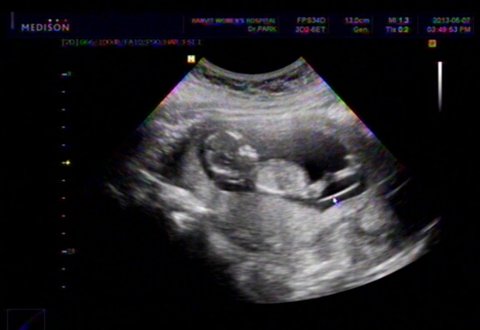

이렇게 다리 긴 태아 보셨어요?

이제 12주.초음파가 마냥 신기한 예비맘이예요.어제 초음파 보고 왔는데..아가가 움직이는 모습을 포착!!다리가 유난히 긴 아가. 싱기방기~~